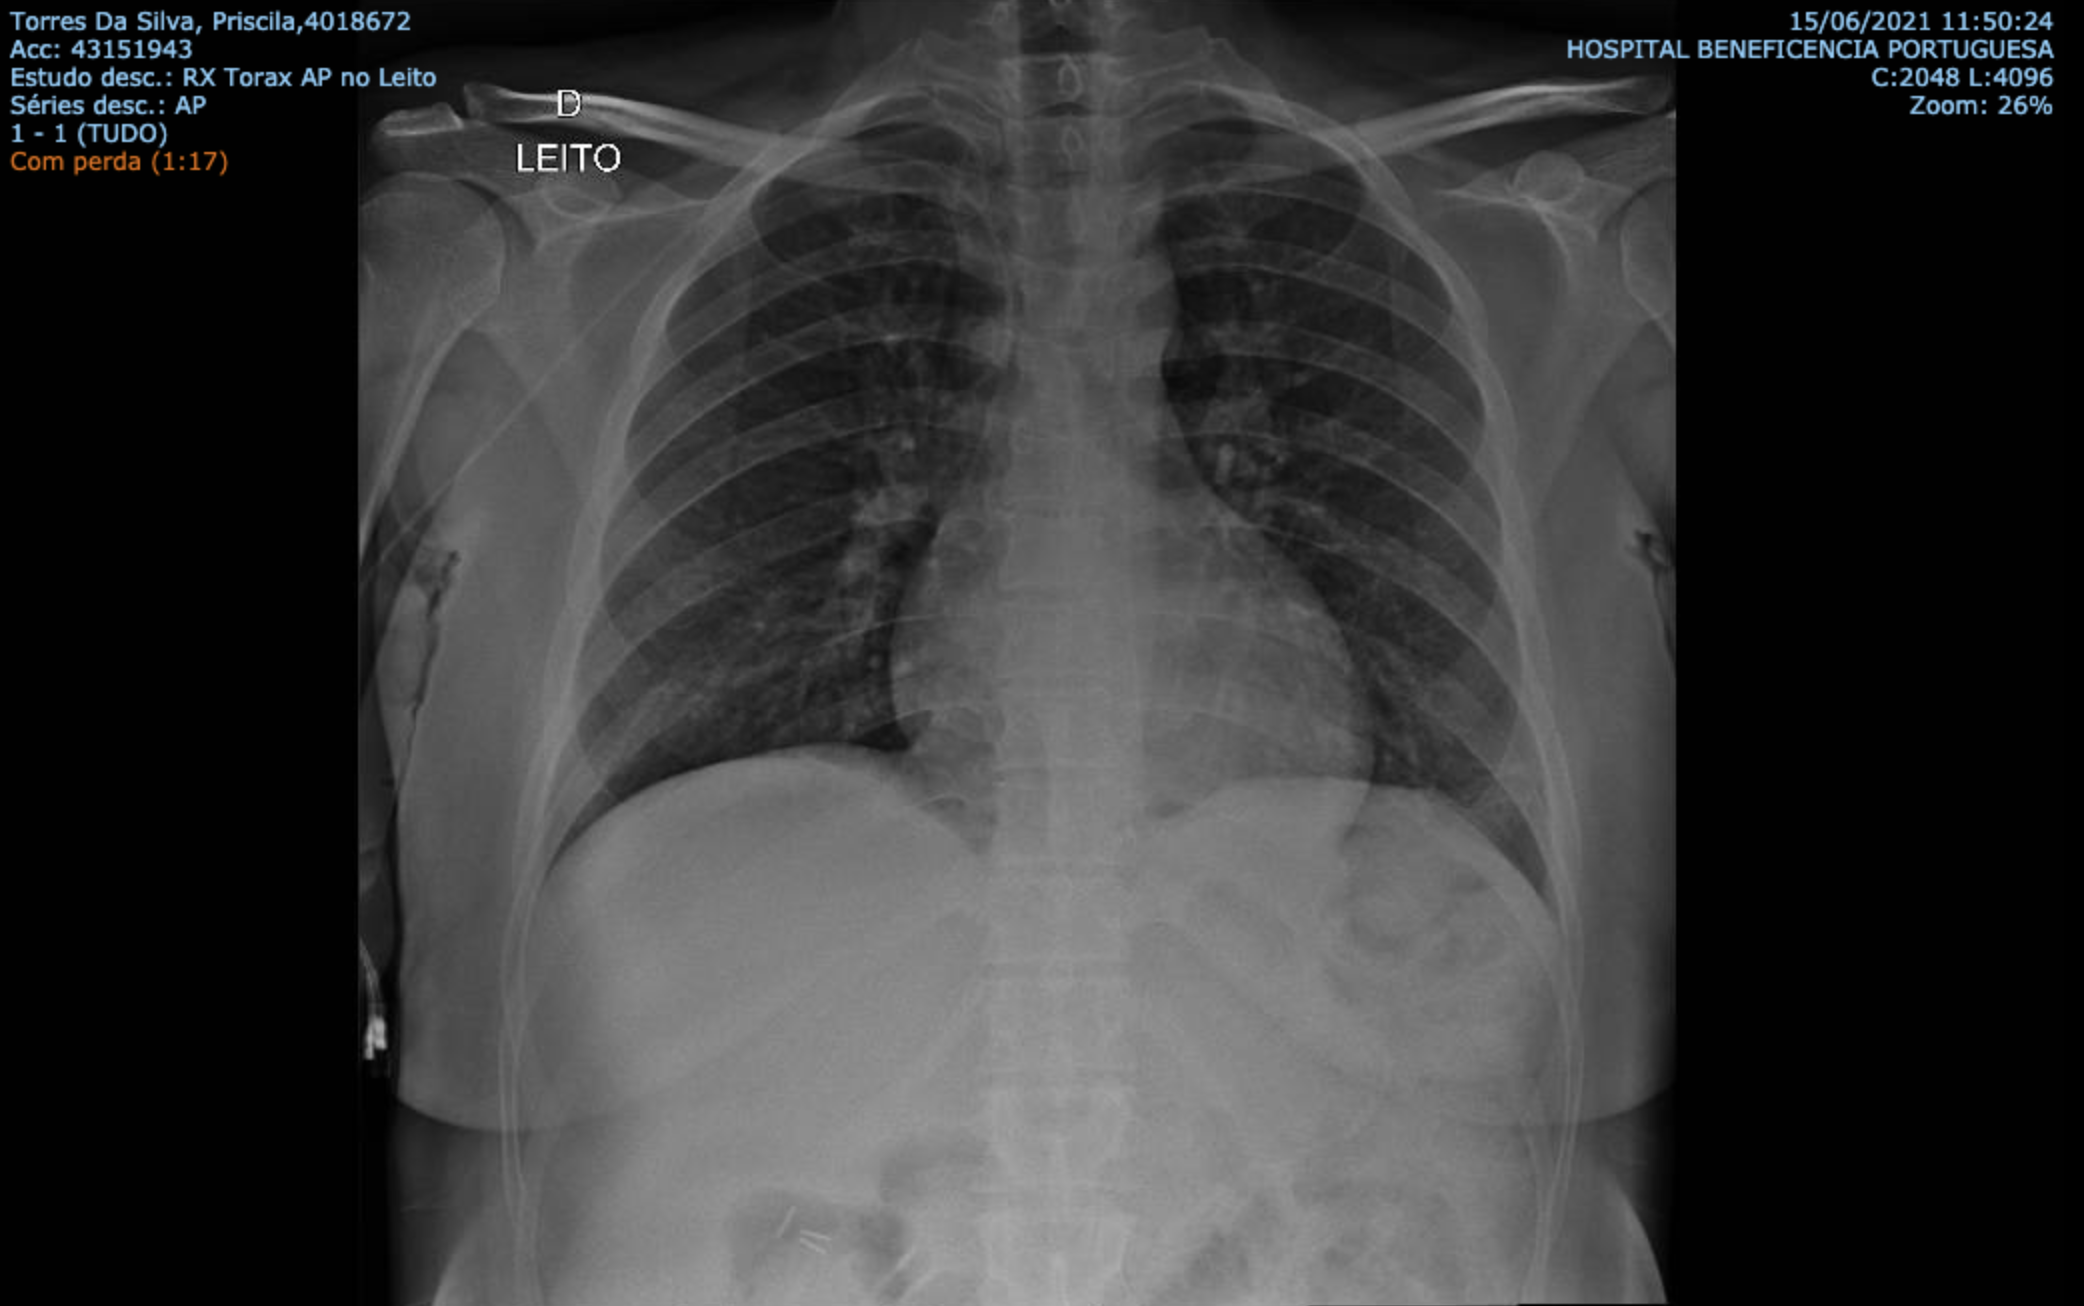

Após o término da inserção do cateter PICC é realizado uma radiografia de tórax para verificar o adequado posicionamento. Um cateter deste tipo, nunca deve ser utilizado antes de ser comprovado o seu posicionamento pela radiografia.